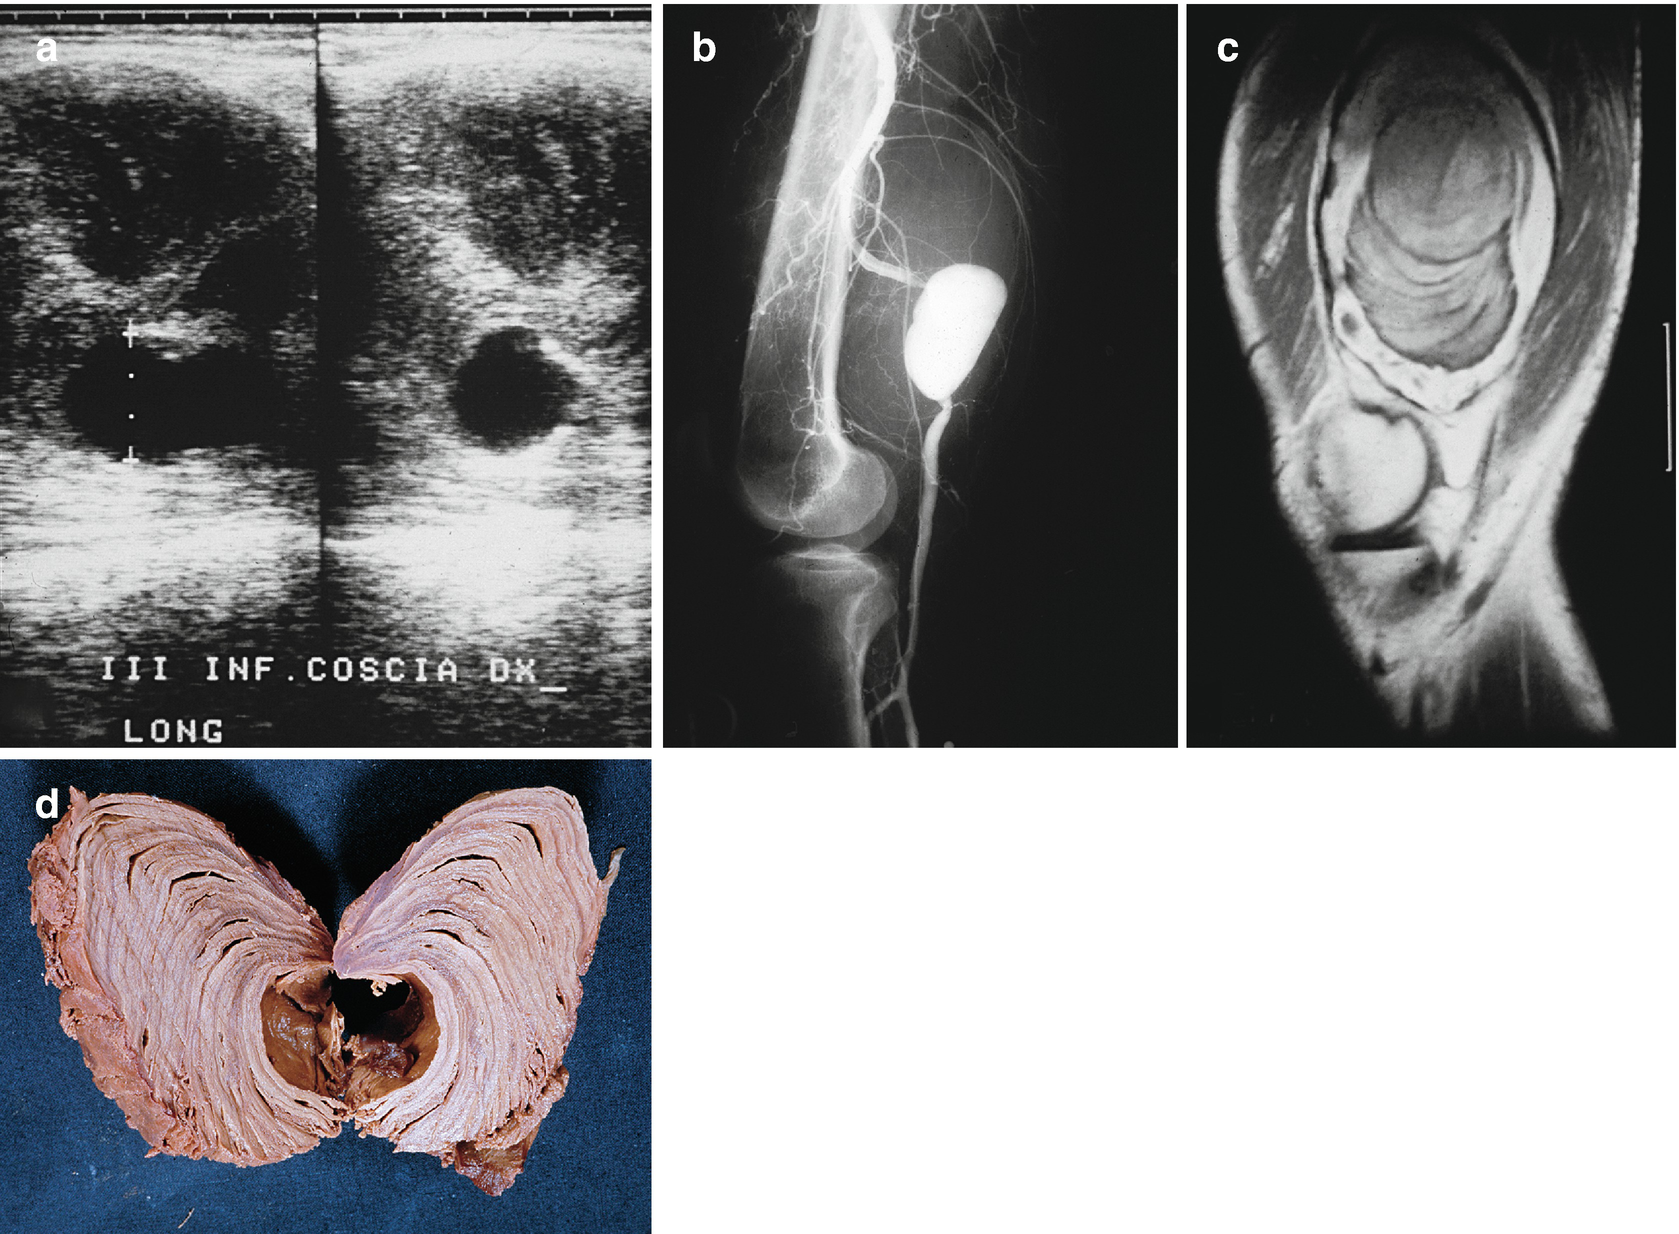

KRAS gene is the most common type of mutation reported in colorectal cancer (CRC) KRAS mutationmediated regulation of immunophenotype and immune pathways in CRC remains to be elucidated 535 CRC patients were used to compare the expression of immunerelated genes (IRGs) and the abundance of tumorinfiltrating immune cells (TIICs) in the tumor microenvironment between KRASmutant and KRAS. It is very frequent and can reach a considerable size Differentiation between lipoma and liposarcoma of low grade malignancy represents an important diagnostic problem, and valuable help in the differential diagnosis is provided by ultrasonography (US), computed tomography (CT), magnetic resonance imaging (MRI), biopsy and/or. For 30 years, Karen Minish has been sharing her gifts with the Bow Valley making us all the richer for it From sharing her incredible voice as a soloist with the Bow Valley Chorus, bringing Christmas joy through her carolling quartet, conducting the hospital choir in Banff, performing, or creating and directing the annual BVC Variety Show, creating incredible works of art, sharing her.

Ultrasound and MRI are the two major diagnostic imaging modalities for evaluating the soft tissues of the thigh Advances in ultrasound technology, including higherfrequency transducers, allow diagnosis of many types of musculoskeletal abnormalities, in many cases with an accuracy similar to that of MRI 1–4Ultrasound has additional advantages compared with MRI, such as lower cost and. Liposarcoma is a cancer that arises in fat cells in soft tissue, such as that inside the thigh or in the retroperitoneum It is a rare type of cancer that bears a resemblance to fat cells when examined under a microscope. Il liposarcoma è, tra le neoplasie della coscia, l’istotipo più comune (1240% nelle varie casistiche);.

It is very frequent and can reach a considerable size Differentiation between lipoma and liposarcoma of low grade malignancy represents an important diagnostic problem, and valuable help in the differential diagnosis is provided by ultrasonography (US), computed tomography (CT), magnetic resonance imaging (MRI), biopsy and/or. La localizzazione di partenza è quasi sempre profonda, a livello dei setti intermuscolari (in particolare per la coscia sono sedi preferenziali il m quadricipite e i m abduttori), o dai tessuti periarticolari, o dal grasso perirenale nei casi di liposarcoma retroperitoneale (5), Friedman e Egan (lO), Perry e Che (25), Edland (4), Mc Neer e. For 30 years, Karen Minish has been sharing her gifts with the Bow Valley making us all the richer for it From sharing her incredible voice as a soloist with the Bow Valley Chorus, bringing Christmas joy through her carolling quartet, conducting the hospital choir in Banff, performing, or creating and directing the annual BVC Variety Show, creating incredible works of art, sharing her.

Exosome isolation and tracking analysis EXOs were isolated from 24 h cell culture media by ultracentrifugation (UC) or ExoquickTC (EQ) (System Biosciences, Mountain View, CA, USA) methods according to standards procedures or manufacturer’s instruction, with minor modifications (Fig 1 a) For exosome purification, serum was depleted of bovine EXOs by ultracentrifugation at 100,000×g for 6. It is very frequent and can reach a considerable size Differentiation between lipoma and liposarcoma of low grade malignancy represents an important diagnostic problem, and valuable help in the differential diagnosis is provided by ultrasonography (US), computed tomography (CT), magnetic resonance imaging (MRI), biopsy and/or.